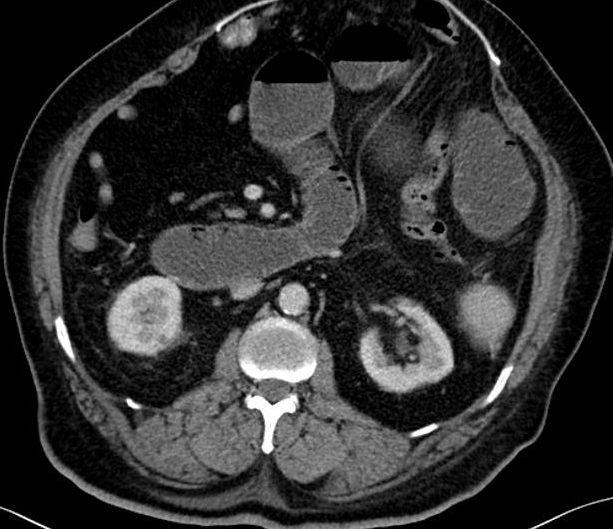

Image TDM :

Image radiologiquer TDM de syndrome de Mirizzi est la

presence de calcul et une epaisissement de la paroi vesicule

biliaire rehaussement hyperdense par le contrast . La dilatation de voie

biliaire pricipale ( canal hepatique commune ) peut se

en voyait . .